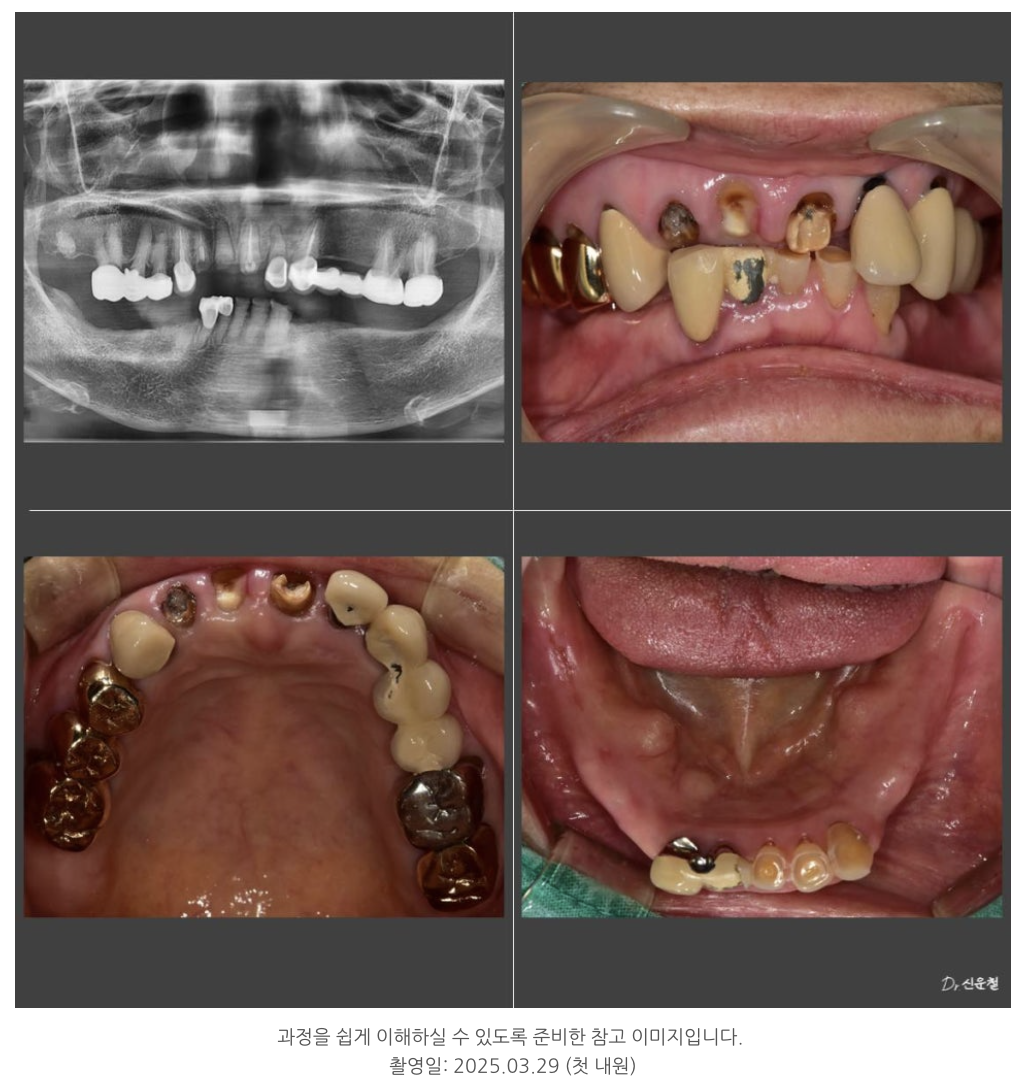

오늘은 80대 환자분의 보험 임플란트와 부분틀니 치료 사례를 소개드립니다.

환자분은 밀양에서 오신 80대 어르신으로,

수년간 치아가 빠진 상태로 지내오셨습니다.

정밀검사 결과, 전체 임플란트는 부담이 커서

다음과 같이 계획했습니다.

윗니: 임플란트 6개 (보험 2개 포함)

아랫니: 부분틀니 + 크라운 보강